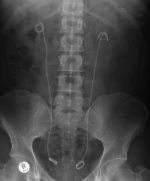

Bilateral stones stentA Southampton surgeon is halving the amount of treatment patients require to remove kidney stones.

Bhaskar Somani, a consultant urological surgeon at Southampton General Hospital, is pioneering the use of a technique to clear both organs in the same procedure, known as bilateral simultaneous ureteroscopy.

It involves using a combination of a viewing instrument, known as a ureteroscope, to visualise and position stones and a laser beam to break them up.

In a recent study, presented at a regional meeting of the British Association of Urological Surgeons, Mr Somani reported 22 bilateral simultaneous ureteroscopies to remove stones of a combined size of 21mm.